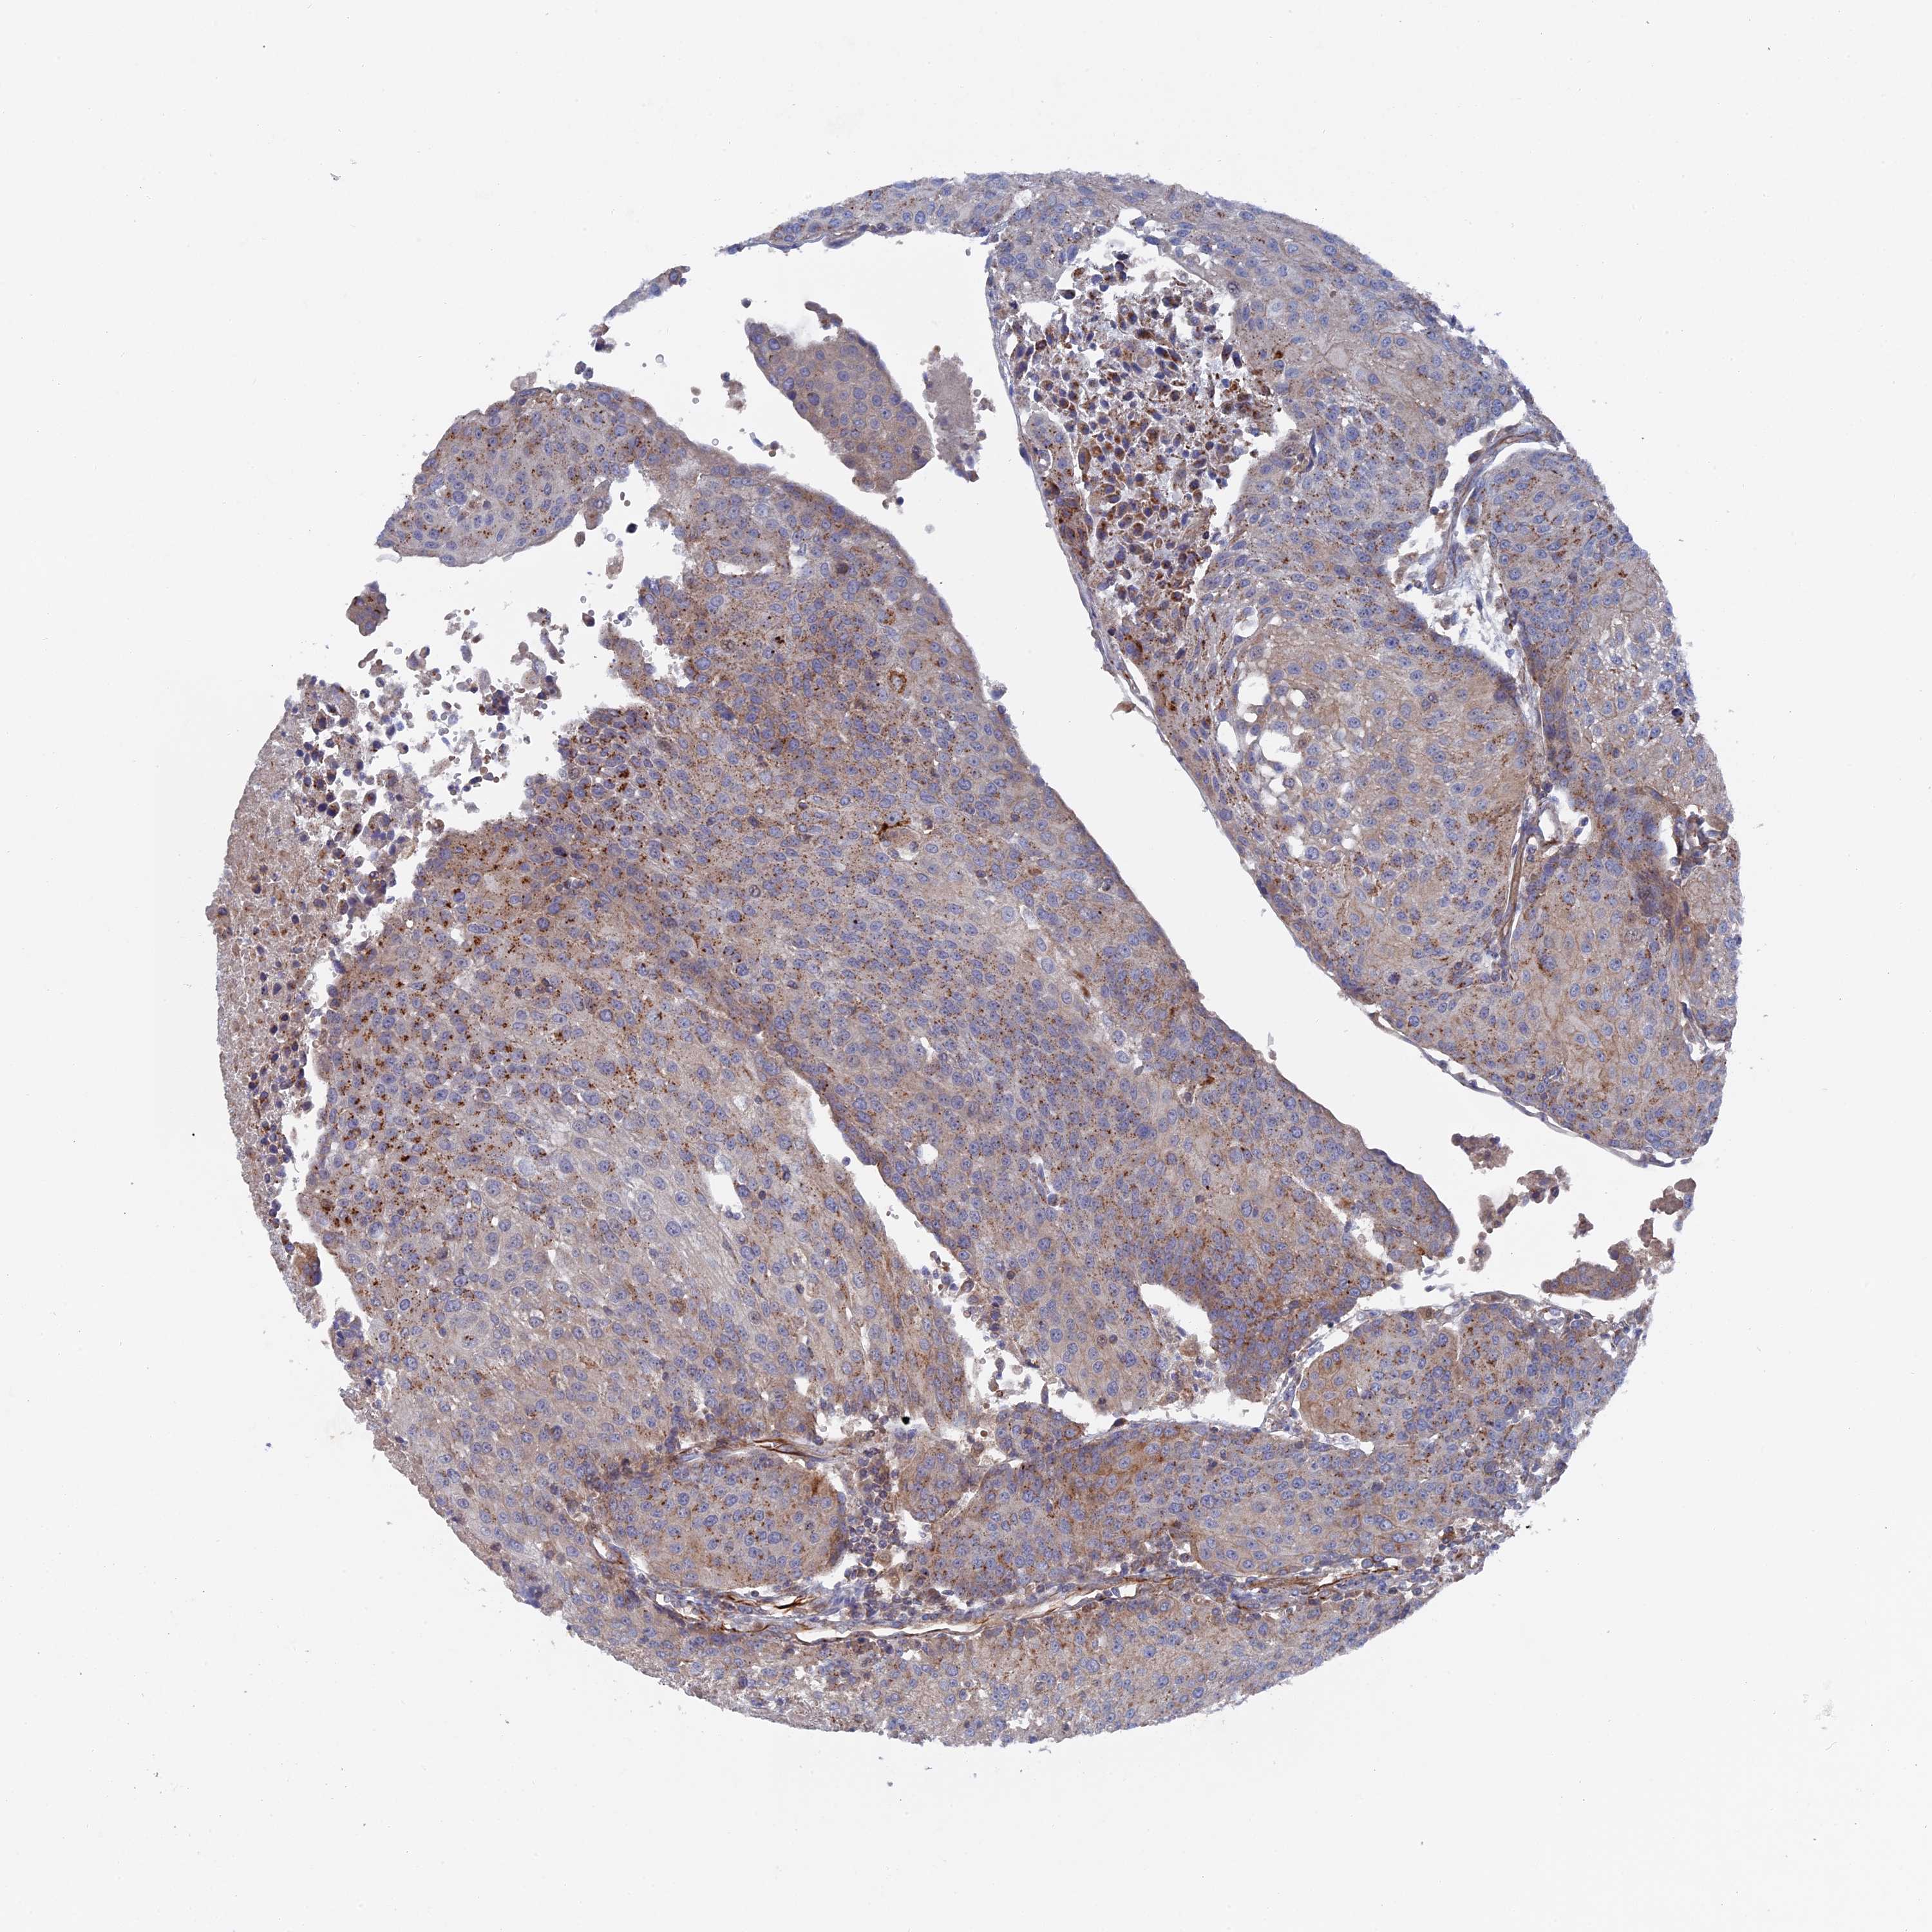

UROTHELIAL CANCER - Protein expressioni

A mouse-over function shows sample information and annotation data. Click on an image to view it in a full screen mode. Samples can be filtered based on level of antibody staining by selecting one or several of the following categories: high, medium, low and not detected. The assay and annotation is described here.

Antibody stainingi

Antibody staining in the annotated cell types in the current human tissue is reported as not detected, low, medium, or high, based on conventional immunohistochemistry profiling in selected tissues. This score is based on the combination of the staining intensity and fraction of stained cells.

Each image is clickable and will lead to virtual microscopy that enables deeper exploration of all samples and also displays staining intensity scores, fraction scores and subcellular localization as well as patient and tissue information for each sample.

Antibody HPA041763

Antibody HPA042096

Staining

High

Medium

Low

Not detected

Intensity

Strong

Moderate

Weak

Negative

Quantity

>75%

75%-25%

<25%

None

Location

Nuclear

Cytoplasmic/membranous

Cytoplasmic/membranous,nuclear

Urothelial carcinoma, Low grade

Urothelial carcinoma, High grade